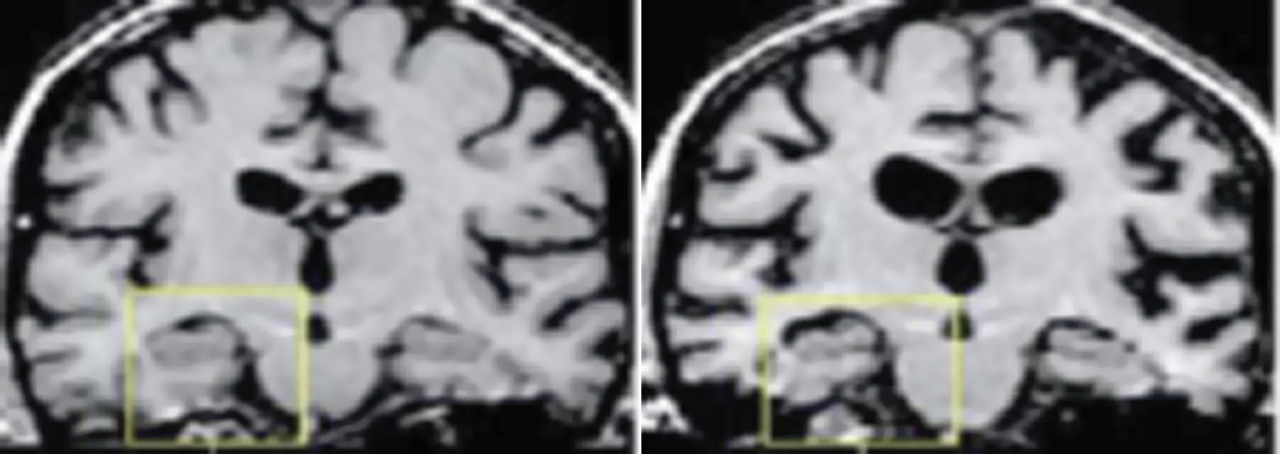

Rechercher un début de troubles cognitifs témoignant d’une maladie dégénérative (Alzheimer, Parkinson ou démence fronto-temporale [DFT]) :

– l’IRM peut montrer une atrophie diffuse ou de l’hippocampe (fig. 5) et/ou des lésions de leucoaraiose ;